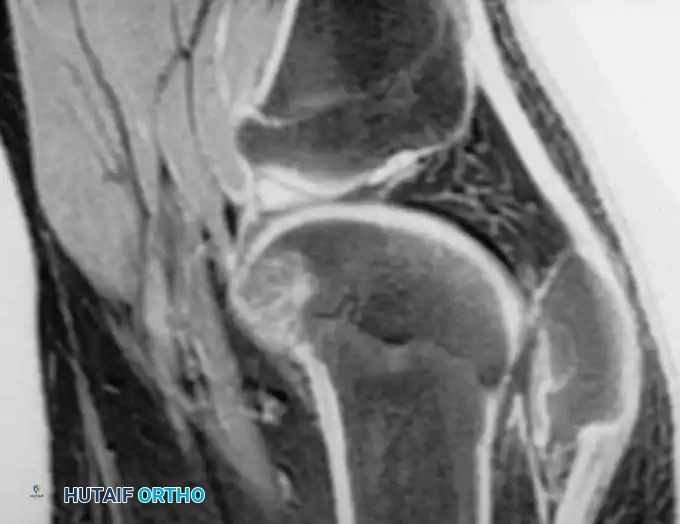

Osteochondritis dissecans (OCD) of the ankle primarily affects the talar dome. The natural history of this lesion in children with open physes is highly favorable compared to adult populations.

Natural History and Imaging

Bauer et al., in a long-term follow-up study (≥ 20 years) of 30 children with ankle osteochondritis, found that only one patient developed severe osteoarthritis. The vast majority experienced complete healing with only minor residual radiographic changes. This is in stark contrast to osteochondritis of the knee, where secondary osteoarthritis is a frequent complication.

Radiographic and MRI evaluation of osteochondral lesions of the talar dome, demonstrating subchondral separation and surrounding edema.